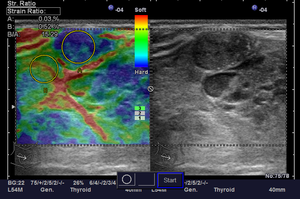

- Исследование с использованием соноэластографии